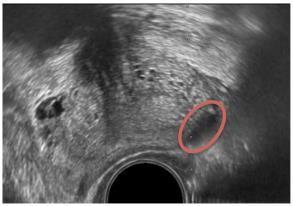

B-mode or grayscale U.S. The most common imaging method for detecting PCa is grayscale or standard B-mode US. BmodeUSisusefulfordistinguishingthezonalarchitectureoftheprostate,withtheoutsidePZappearing moreechogenic thantheinteriorCZandTZ.Grayscaletransrectalultrasonography(TRUS)imagingwasfirstusedbyHodgeetal.toguidesix biopsyneedlesintotheprostatein1989.Sincethen,randomandsystematicprostatebiopsieshavebeenthegoldstandard for detecting PCa,and this method has served asitsfoundation,alongwiththe additional targeting of hypoechoic lesions (cancertissuewithcellulararchitecturedefectsappearslessechogenicthannormaltissueongrayscaleUS,asshowninFig. 3). [6,7] An extended sextant 12-core biopsy, aiming for the apical and lateral parts of the PZ where the cancer is most likelytobehiding,hasbeenthesubjectofnumerousdiscussionsonhowtomaximizeitslikelihoodofdetectingcancer.[8]

Fig – 3 B-mode US image of the prostate depicting hypoechoic lesion (red oval).